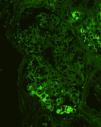

An 80-year-old Japanese man with stage G3a chronic kidney disease due to diabetes mellitus was admitted to the general medicine service for management of right haemopneumothorax after a motor vehicle accident and subsequent empyema caused by methicillin-sensitive Staphylococcus aureus treated with four weeks of intravenous cefazolin and drainage. The patient was seen in nephrology consultation for a rise in serum creatinine level from 1.4mg/dl upon admission to 5.3mg/dl (estimated glomerular filtration rate of 9ml/min/1.73m2) and purpuric lesions on the bilateral lower extremities. At the general medicine service, oral glucocorticoid was initiated for a presumed diagnosis of IgA vasculitis (Henoch-Schönlein purpura). However, the kidney function continued to worsen, and oliguria ensued despite infusion of lactated ringer's solution. Upon physical examination, he was not in distress. The blood pressure was 110/78mmHg. There were trace pretibial oedema and purpuric lesions on the bilateral legs. Urinalysis showed >100 red blood cells per high-power field (70% dysmorphic) and 5.2g/24h of proteinuria. Immunological analysis showed that increased immunoglobulins (IgG 1427mg/dl; IgA 1373mg/dl; IgM 48mg/dl) and decreased complement levels (C3 77mg/dl; C4 30mg/dl; CH50 44IU/ml). Antinuclear antibodies, antimyeloperoxidase antibodies, antiproteinase 3 antibodies, and a glomerular basement membrane antibody were negative. Renal biopsy showed 10 glomeruli, 4 of them sclerosed and 2 with endocapillary proliferation (Fig. 1). There was a mild interstitial infiltrate of polymorphonuclear cells, and the arteries had no significant lesions. Immunofluorescence microscopy showed diffuse depositions of IgA (Fig. 2) and C3. Electron microscopy could not be performed because of insufficient specimens. Based on clinical features and pathologic findings, IgA-IRGN was diagnosed. Intravenous cefazolin was administered for another four weeks, and oral glucocorticoid was tapered and stopped gradually without relapse of infection. However, the patient progressed to end-stage kidney disease even after 20mg of olmesartan was initiated.